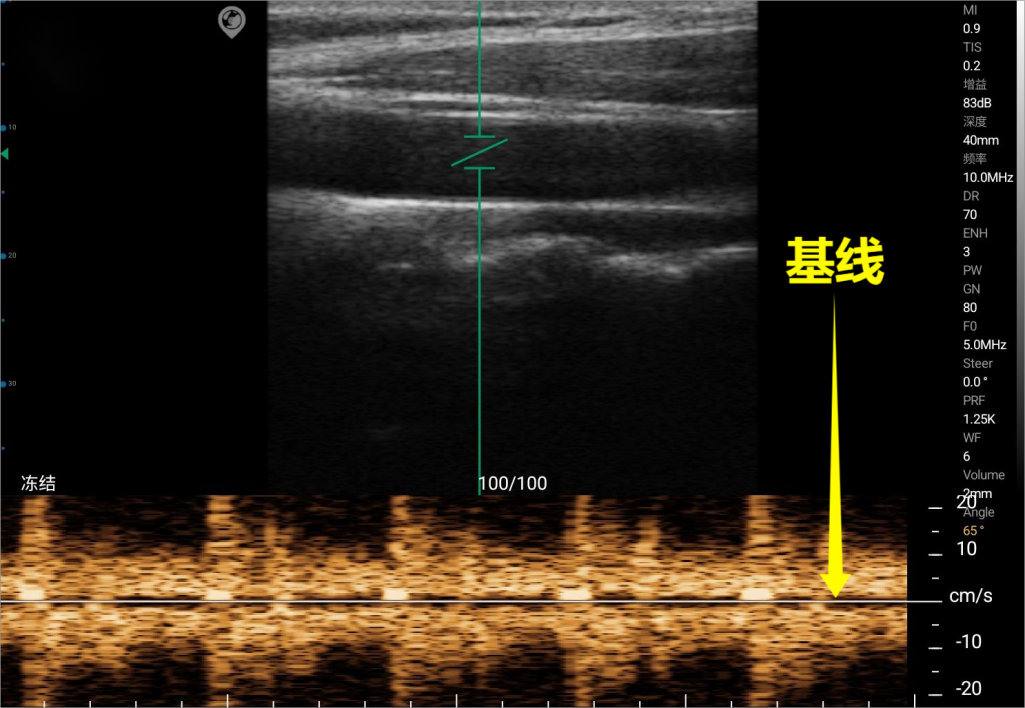

Baseline